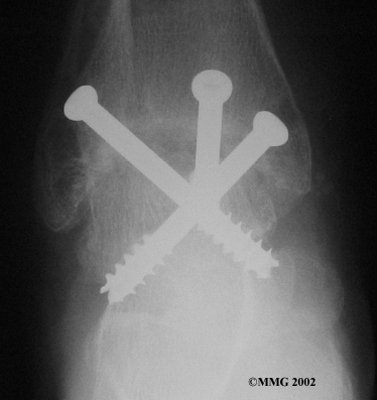

It is important when the surfaces are removed that the angles of the cut surfaces are correct. When the tibia is brought against the talus, the foot should be at a right angle to the lower leg. Once the cuts are made the bones must be held in place while they fuse. This can be done using large metal screws and metal plates if necessary. The screws are usually under the skin and are not removed unless they begin to rub and cause pain.

Inserting the screws

After ankle fusion, the physical therapists at FYZICAL East China can help you learn to walk smoothly and without a limp. Although time needed for recovery varies among patients, an ankle brace will typically replace your cast after eight to 12 weeks. Your surgeon will take X-rays frequently to see if the bones are fusing together. You will probably need to use crutches during the time you wear the cast. As the fusion grows stronger, you will begin to put more weight on your foot when walking.